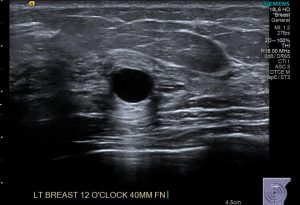

Το υπερηχογράφημα απεικονίζει την υφή του οργάνου καταγράφοντας την παρουσία διαφόρων εστιών μέσα στο όργανο είτε αυτές είναι κυστικές, είτε συμπαγείς. Με το απλό υπερηχογράφημα, χρησιμοποιώντας δεδομένα όπως το σχήμα, το περίγραμμα ή η σαφήνεια των ορίων μπορούν να εξαχθούν συμπεράσματα για το αν μία βλάβη είναι καλοήθης ή ύποπτη για κακοήθεια. Νεότερες τεχνικές όπως η έγχρωμη υπερηχογραφία με την οποία καταγράφεται η αιμάτωση της βλάβης καθώς και η Ελαστογραφία με την οποία εκτιμάται ο βαθμός σκληρότητας της βλάβης δίδουν σημαντικές πληροφορίες για το αν η βλάβη είναι καλοήθης ή κακοήθης. Τέλος με τη βοήθεια των υπερήχων, μπορεί να οδηγηθεί λεπτή βελόνα παρακέντησης, ώστε να ληφθεί δείγμα από συγκεκριμένη περιοχή για κυτταρολογική εξέταση, είτε κόπτουσα βελόνα προκειμένου να ληφθεί υλικό για ιστολογική εξέταση.